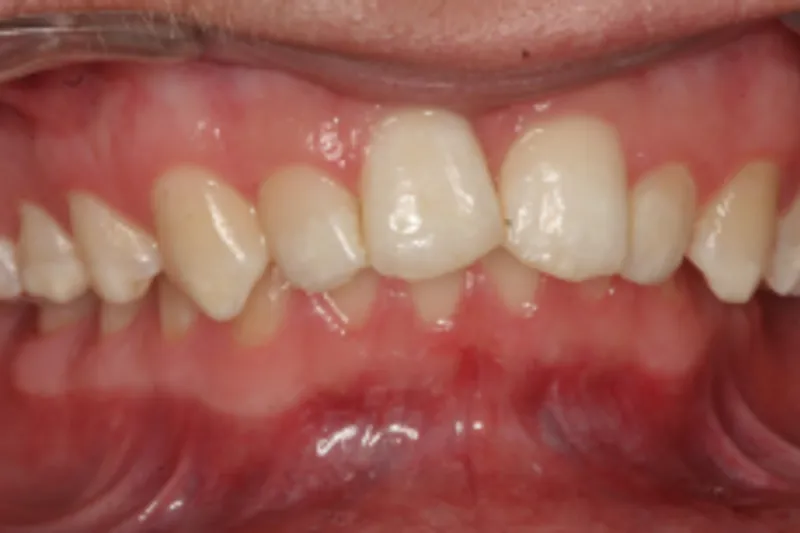

En 15-årig dreng med infantil autisme blev henvist fra Hjørring Kommunes Tandpleje til Kæbekirurgisk Afdeling, Aalborg Universitetshospital, for ortodontisk-kirurgisk behandling af et stort horisontalt maksillært overbid uden kontakt på nogen af tænderne. Den vækstbetingede kæbedeformitet blev korrigeret ved hjælp af ortodonti og mandibulær midtlinjedistraktionsosteogenese efterfulgt af en sektioneret Le Fort I-osteotomi og bilateral sagittal splitosteotomi.

A 15-year-old boy with infantile autism was admitted from Hjørring municipal dental care to the Department of Oral and Maxillofacial Surgery, Aalborg University Hospital for orthognathic surgery of a large horizontal maxillary overjet without occlusal contact between the teeth. The dentofacial deformity was corrected using orthodontics and mandibular midline distraction osteogenesis followed by a segmented Le Fort I osteotomy and bilateral sagittal split osteotomy.